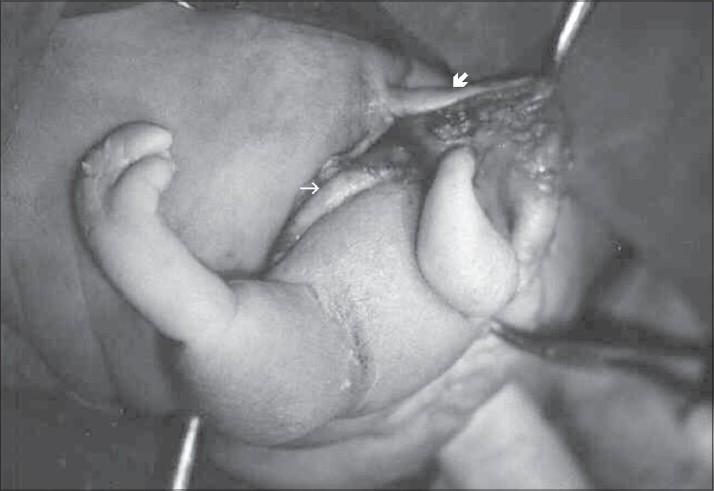

Fetus in fetu is a rare condition that has been defined as the presence of one of the twins in the body of the other. It is most frequently located in retroperitoneal area; however, it has been reported in other locations as well. This report presents two cases of "fetus in fetu" cases: one located in the retroperitoneal area and the other in the sacrococcygeal area.

胎中胎是一种罕见的情况,被定义为双胞胎中的一个位于另一个体内。它最常位于腹膜后区域;然而,其他部位也有相关报道。本报告展示了两例“胎中胎”病例:一例位于腹膜后区域,另一例位于骶尾区域。